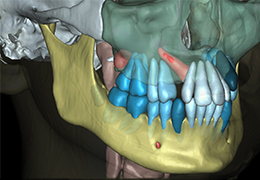

View X-Ray CT & MRI Scans Fast and Easily

FREE and easy to use 3D DICOM Viewer – for surgeons and patient education

Designed for surgeons, Pro Surgical 3D makes it easy to view patient scans quickly. Pro Surgical 3D facilitates the optimal 3D treatment and assessment workflows based on X-ray CT and MRI scans – and best of all, it’s FREE!

Everyone – including surgeons, patients and their loved ones – benefits from being better informed by the wealth of information buried within CT and MRI scans. Pro Surgical 3D gives surgeons more information to develop optimal treatment plans for patients. It also helps patients and their support group better understand their medical condition and proposed treatment options.

Performs 3D reconstruction and volume rendering.